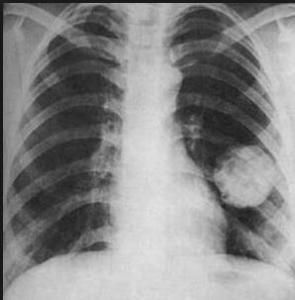

肺腫瘤X光片肺部腫瘤的預防勝於治療,主要分為三級預防。一級預防針對健康人群,主要包括不吸菸,遠離二手菸污染。儘量避免室外空氣污染、廚房油煙。選用環保型裝修材料。營養均衡,多食穀物、蔬菜、水果。保持樂觀、積極的生活態度,提高心理適應力。二級預防早診、早治針對高危人群,主要針對40歲以上長期吸菸者,吸菸20年以上,20歲以下開始吸菸機每天吸菸20支以上,經常接觸煤煙、煤焦油和油煙者,接受過量放射線照射者(採礦者等)、慢性咳嗽、痰中帶血者及有肺癌家族史者。高危人群最好能每年定期全面體檢,有條件的行CT檢查。如出現刺激性咳嗽、血痰火咯血等症狀應及時醫院就診。三級預防即康復性預防,肺癌患者應遵醫囑按期到醫院複查。

X線檢查這是診斷肺癌的一個重要手段。大多數肺癌可以經胸部x線攝片和CT檢查獲得臨床診斷。中心型肺癌早期X線胸片可無異常徵象。當癌腫阻塞支氣管,排痰不暢,遠端肺組織發生感染,受累的肺段或肺葉出現肺炎徵象。若支氣管管腔被癌腫完全阻塞,可產生相應的肺葉或一側全肺不張。當癌腫發展到―定大小,可出現肺門陰影,由於腫塊陰影常被縱隔組織影所掩蓋,需作胸部X線斷層攝影和CT檢查才能顯示清楚。

在斷層x線片上可顯示突入支氣管腔內的腫塊陰影,管壁不規則、增厚或管腔狹窄、阻塞。支氣管造影可顯示管腔邊緣殘缺或息肉樣充盈缺摜,管腔中斷或不規則狹窄。腫瘤侵犯鄰近的肺組織和轉移到肺門及縱隔淋巴結時,可見肺門區腫塊,或縱隔陰影增寬,輪廓呈波浪形,腫塊形態不規則,邊緣不整齊,有時呈分葉狀。縱隔轉移淋巴結壓迫膈神經時,可見膈肌抬高,透視可見膈肌反常運動。氣管隆凸下腫大的轉移淋巴結,可使氣管分叉角度增大,相鄰的食管前壁,也可受到壓迫。晚期病例還可看到胸膜腔積液或肋骨破壞。